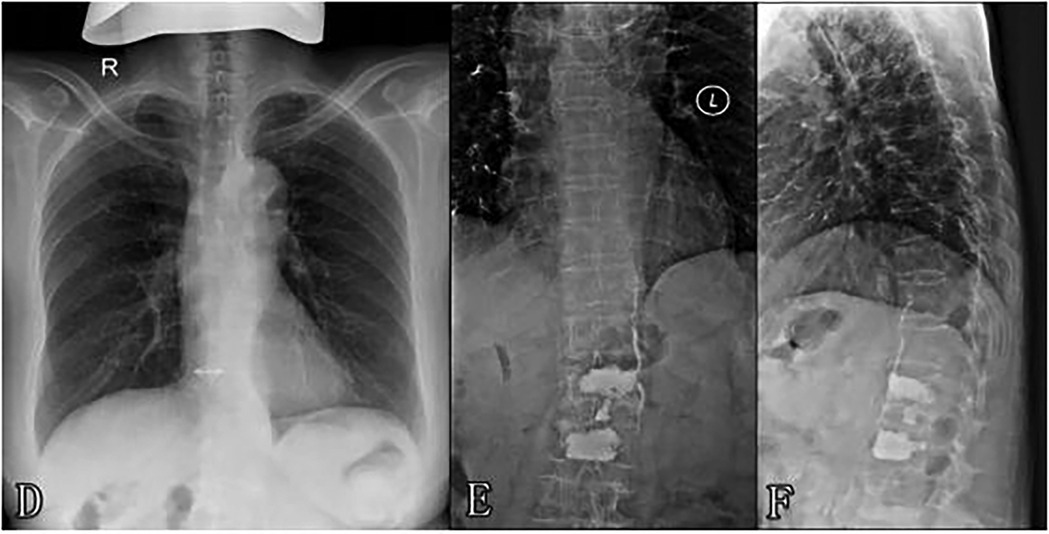

A 69-year-old woman was admitted to our hospital due to refractory back pain for approximately one month. Preoperative evaluation revealed that the patient had a bone mineral density T-score of −3.2 at L1-L4, indicating severe osteoporosis, imaging findings from MRI showing fresh osteoporotic vertebral compression fractures at L1 and L2 (characterized by T1-weighted hypointensity and T2-weighted hyperintensity with edema), while lower extremity Doppler ultrasound detected no pre-existing venous thrombosis. The routine preoperative medical evaluation was normal. Given her symptoms and spine images, she was treated with percutaneous vertebroplasty under local anesthesia (1% lidocaine) with continuous monitoring of heart rate, blood pressure, and oxygen saturation. Bone cement was typically infused into the vertebral body using a unilateral transpedicular approach, with intermittent anteroposterior and lateral fluoroscopy guidance. The percutaneous vertebroplasty procedure for L2 was completed successfully and approximately 4.5 ml of bone cement was infused (polymethylmethacrylate, viscosity: high, mixed for 3 min before injection). Then, the percutaneous vertebroplasty procedure for L1 was performed as follows. When the injection volume reached approximately 1.5 ml, anterior cement leakage in the paravertebral venous system was detected on lateral fluoroscopy. Immediately, vital signs were observed to be continuing smoothly with no obvious fluctuations (HR 72 bpm, BP 135/85 mmHg, SpO2 99%). Additionally, there were no complaints of cardiorespiratory discomfort by the patient. As the vertebral fill was inadequate, we continued the bone cement injection procedure. However, the trajectory tracking of cement leakage in the paravertebral venous system was gradually prolonged with continuous additional cement injection (Figure 1). When the cement injection dose reached approximately 4 ml, cement disk space extravasation was detected and we terminated the procedure at that time. The postoperative outcome was seemingly good and had no symptoms such as dyspnoea, coughing, haemoptysis, dizziness or palpitation. However, the postoperative thoracolumbar x-ray presented that multiple tubular and branching cement emboli were scattered throughout the lungs (Figure 2). Intraoperative lateral fluoroscopy data were analysed retrospectively, and we detected that sustained cement injection resulted in the migration of the distal part of the prolonged cement leakage tracks in the paravertebral venous system on the last lateral fluoroscopy. The subsequent treatment consisted of two days of conventional postoperative treatment and electrocardiogram monitoring, with no use of anticoagulation. The patient's vital signs continued smoothly until discharge. The patient was satisfied with the operation because her back pain was significantly relieved. With a one-year clinical follow-up after discharge, she remained asymptomatic. During the follow-up after discharge, it was noted that the patient developed pneumonia more than one year after leaving the hospital. Computed tomography (CT) at the local hospital confirmed the presence of bone cement emboli within the pulmonary artery branches, as illustrated in Figure 3, following successful treatment, the patient recovered uneventfully and was discharged from the hospital.

Figure 1. (A,B) Trajectory tracking of cement leakage into the paravertebral venous system was gradually prolonged with sustained injection. (B,C) Cement leakage migration. (Arrow: migration of the distal part of the prolonged cement leakage into the paravertebral venous system).